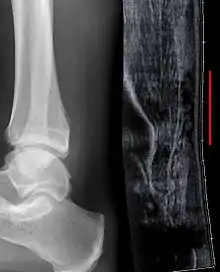

Sometimes an ultrasound scan may be required to clarify or confirm the diagnosis and is recommended over MRI.[10] MRI is generally not needed.[11]

Imaging

Musculoskeletal ultrasonography can be used to determine the tendon thickness, character, and presence of a tear. It works by sending extremely high frequencies of sound through the body. Some of these sounds are reflected back off the spaces between interstitial fluid and soft tissue or bone. These reflected images can be analyzed and computed into an image. These images are captured in real time and can be very helpful in detecting movement of the tendon and visualising possible injuries or tears. This device makes it very easy to spot structural damages to soft tissues, and consistent method of detecting this type of injury. This imaging modality is inexpensive, involves no ionizing radiation and, in the hands of skilled ultrasonographers, may be very reliable.

Radiography can also be used to indirectly identify Achilles tears. Radiography uses X-rays to analyse the point of injury. This is not very effective at identifying injuries to soft tissue. X-rays are created when high energy electrons hit a metal source. X-ray images are acquired by utilising the different attenuation characteristics of dense (e.g. calcium in bone) and less dense (e.g. muscle) tissues when these rays pass through tissue and are captured on film. X-rays are generally exposed to optimise visualisation of dense objects such as bone while soft tissue remains relatively undifferentiated in the background. Radiography has little role in assessment of Achilles' tendon injury and is more useful for ruling out other injuries such as calcaneal fractures.[12]